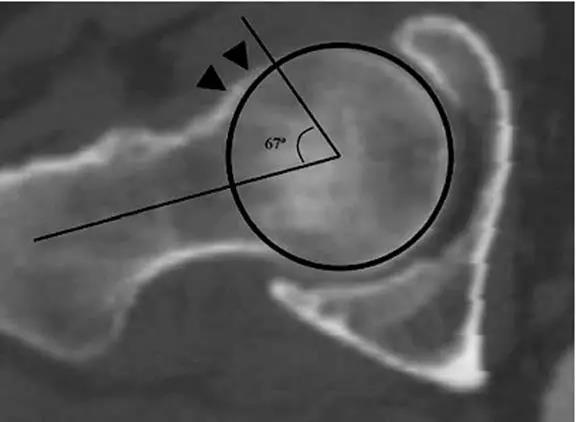

- 股骨头中心O点为圆心,股骨头正常最大半径为r,从股骨头颈连接处骨质与这个圆的交点(A点)到股骨头中心点作直线OA,此直线与股骨颈中轴线OB的交角为α角。

- 反映股骨颈骨赘突出程度,α角越大,越容易发生前上方股骨头颈与髋臼唇的撞击。

- FAI组中该角平均为74.0°±5.4°,正常对照组为42.0°±2.2°。

- α角>50°是诊断FAI的临界值。